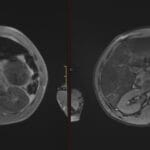

- Radiology Cases: Images with a to-the-point discussion highlighting the specific diagnostic criteria.

Latest Radiology Cases